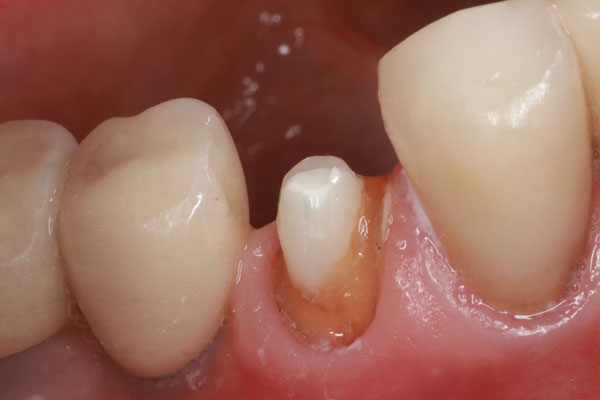

Un paciente se presentó con un diente roto (es decir, el diente No. 28) que requirió tratamiento de conducto. Hubo una pérdida significativa de estructura dental; por lo tanto, se consideró necesario un tratamiento posterior y central para sostener una corona (Figura 1). El paciente fue anestesiado y se excavó cualquier caries restante. Después de obtener, evaluar y medir una radiografía, se utilizó un taladro para eliminar aproximadamente dos tercios de la longitud del material de obturación del conducto radicular (Figura 2). Se tomó otra radiografía para confirmar que la profundidad alcanzada era correcta. A continuación, se probó primero el sistema de poste ajustable único (Splendor SAP, Angelus) sin el manguito para determinar si estaba completamente asentado (Figura 3). Luego se probó con el manguito y se consideró que encajaba bien (Figura 4).

Imagen 3 Prueba de la publicación Splendor SAP para garantizar asientos completos.